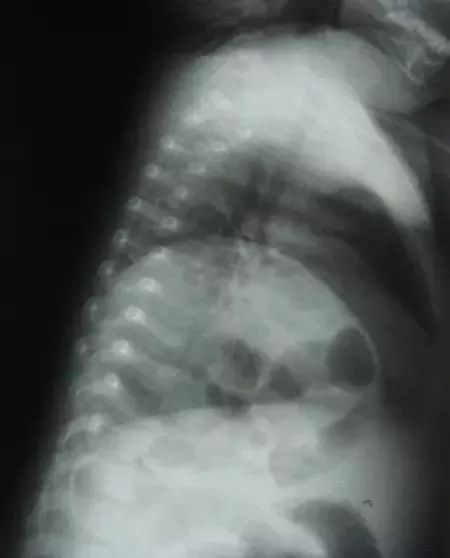

全血细胞计数显示13×10³/µL ,白细胞计数:13×10^9/L,中性粒细胞45%、淋巴细胞42%、嗜酸性粒细胞3%。暂无血气分析。X线如下图,拍片过程中未见右侧膈肌移动。

根据临床表现,辅助检查如X线检查可见患侧膈肌升高,可升到第三、四前肋间隙高度,膈下紧贴胃泡,膈肌厚度明显变薄,胸透可见患侧膈肌活动受限或消失,有时可见矛盾运动,尤其是后天性膈膨出者更为明显。